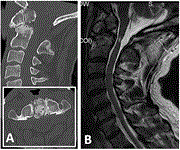

Dynamic myelopathy as a result of C1 posterior arch aplasia and os odontoideum. A case report

Wen Jie Choy and others

Journal of Surgical Case Reports, Volume 2020, Issue 3, March 2020, rjaa019, https://doi.org/10.1093/jscr/rjaa019